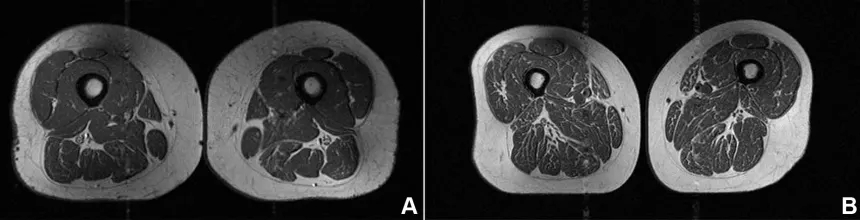

Προειδοποίηση επιστημόνων για τα υπερεπεξεργασμένα τρόφιμα: Η μαγνητική γυναίκας με τους μηρούς-μπριζόλα και ο «σιωπηλός» κίνδυνος - Το Γεγονός